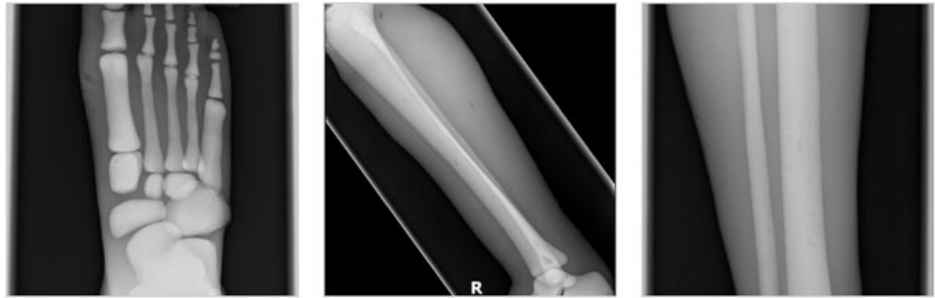

成人腿部模體,用于 X 射線 CT 和超聲波的成人腿部(肌肉)模型是一種基于人類男性腿部平均解剖結(jié)構(gòu)設(shè)計(jì)的逼真模型。它具有所有基本的骨骼和

軟組織特征,使其成為學(xué)習(xí)、研究和測試醫(yī)學(xué)成像設(shè)備的理想工具。 模體可用于研究不同方向和定位技術(shù)的多種診斷性 X 射線 CT 和超聲程序。根據(jù)

要求,該產(chǎn)品可以根據(jù)不同的病理進(jìn)行定制,也可以用于特定的培訓(xùn)應(yīng)用。 模體尺寸:965.2 x 254 x 177.8 毫米,重量:12kg(約)